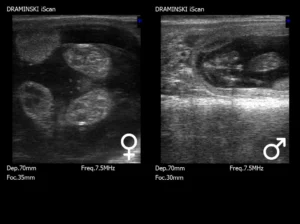

Ultrasonografia dopplerowska to coraz częstszy gość w praktyce terenowej lekarzy weterynarii zajmujących się rozrodem bydła. Choć technika badania wygląda podobnie jak klasyczne USG rektalne, to kluczową różnicą jest możliwość oceny przepływu krwi w naczyniach krwionośnych. Ta jedna funkcja otwiera zupełnie nowe możliwości diagnostyczne i pozwala na bardziej świadome zarządzanie rozrodem w stadzie.

Mniej „strzałów w ciemno”. Można ocenić, czy pęcherzyk jest „aktywny” i rokuje na owulację, czy już ulega atrezji. W przypadku ciałka żółtego — kluczowego dla utrzymania ciąży — Doppler pozwala stwierdzić, czy jest funkcjonalne, zanim jeszcze zmieni rozmiar. To szczególnie przydatne przy ocenie niepowodzenia inseminacji – możliwe nawet przed 28. dniem po kryciu!

W embriotransferze Doppler też robi robotę – umożliwia lepszą selekcję biorczyń, bo dobrze unaczynione ciałko żółte to większa szansa na skuteczne przyjęcie zarodka. Badania pokazują, że stopień perfuzji CL jest lepszym wskaźnikiem niż jego rozmiar czy nawet poziom progesteronu.